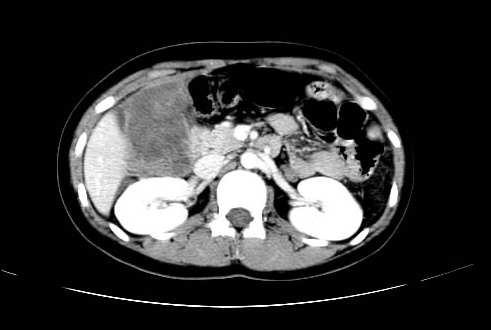

女 16岁  右上腹痛一天,无其他不适

肿块最大径位于十二指肠降段与水平段移行处,并且与肝脏压迹呈“0”形征,可以考虑位于肝外并与胃肠道关系紧密,考虑胃肠道间质瘤(gist)可能较大,须除外神经节起源肿瘤。

肿块与十二指肠关系密切,支持间质瘤诊断.肝脏与结肠均为受压改变.

右下腹巨大肿快,密度不均匀,内见坏死低密度区,边界清楚,与周边胀器明显有分界,未见强化,多考虑来源于间叶组织的良性肿物.

我坚决反对您的观点,该病例定位:横结肠肝曲与升结肠之间的肠系膜及部分肠壁。请看下图:

病灶巨大,少部分向肠腔内生长,大部分向长腔外生长。其密度不均匀,增强显示明显不均匀强化,并见有大片状始终不强化的不规则坏死液化区。虽然病灶中上部形态尚可,病人又如此年轻,但中下部形态、密度、强化特点强烈提示为恶性病灶。综上,我考虑本病例为:恶性胃肠道间质瘤。